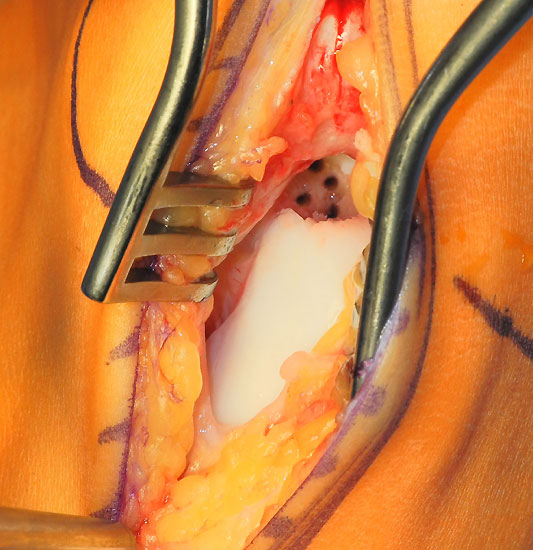

Operationstechnik (Fotos und Video)

Je nach Lage des Knorpeldefektes sind verschiedene Zugänge möglich. Ziel ist einen guten Zugang zum Defekt zu erreichen bei gleichzeitiger Vermeidung einer Innenknöchelosteotomie.

Die Darstellung der weiteren Operationstechnik erfolgt am Beispiel eines medialen Zugangs bei einer Osteochondrosis dissceans mit subchondraler Zyte der medialen Talusschulter (siehe MRT Abbildung 1).